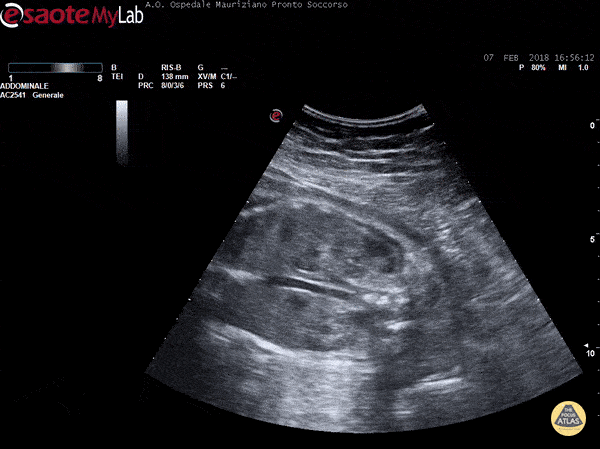

Pulsating fetal aorta Marco Garrone

https://www.thepocusatlas.com/aorta